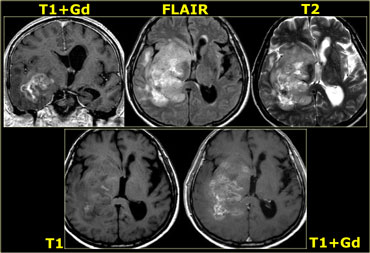

GBM with patchy enhancement and cystic component with ring enhancement GBM with patchy enhancement and cystic component with ring enhancement

On the left is an example of a glioblastoma multiforme (GBM).

The enhancement indicates that this is a high-grade tumor, but only parts of it enhance.

Notice that there is also a cystic component with ring enhancement.

The tumor cells probably extend beyond the area of edema as seen on the FLAIR image.

This is because gliomas grow infiltratively into normal brain - initially without any MR changes.

Patchy enhancement (2)

On the left are images of a tumor located in the right hemisphere.

Although is a large tumor, the mass-effect is limited.

This indicates that there is marked infiltrative growth, a characteristic typical for gliomas.

Notice the heterogeneity on both T2WI and FLAIR.

There is patchy enhancement.

All these findings are typical for a GBM.

Virtually no other tumor behaves in this way.